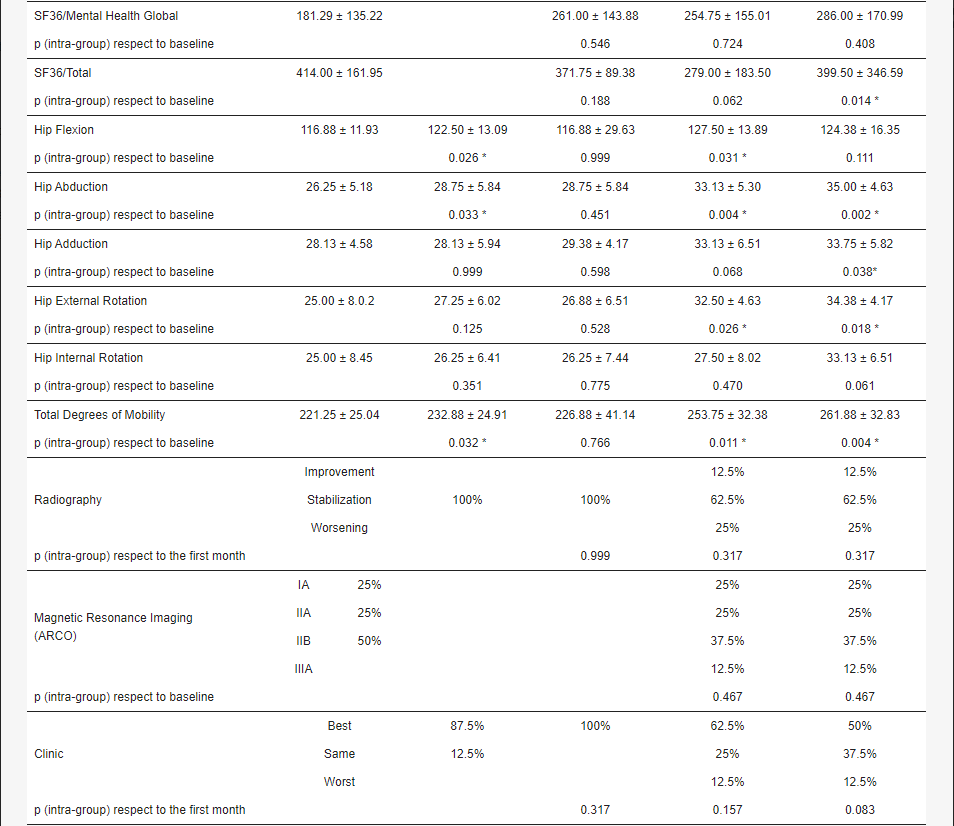

關于影像學研究,在12個月的隨訪期間,在影像學演變中觀察到了一些發現(圖1和圖2)。

首先,方向的變化從第六個月開始出現在所有病例中,而在早期階段并不明顯。其次,62.5%的患者 ( n=5) 在手術后的第一年內實現了影像穩定。第三,兩名患者 (25%) 出現壞死區進展,而一名 (12.5%) 患者出現明顯的再骨化跡象。盡管觀察到描述性差異,但后一個參數的p值在統計學上并不顯著。